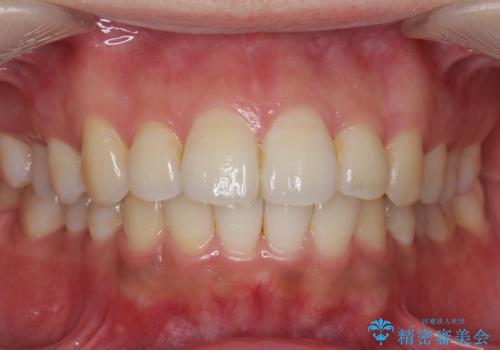

[ 前歯のねじれ・がたつき ] マウスピース矯正

![[ 前歯のねじれ・がたつき ] マウスピース矯正の症例 治療前](https://seimitsushinbi.jp/wp/wp-content/uploads/2024/02/4007c6479f6bce11863dcdd32ed5e39b-500x350.jpg?v=1708502552)

![[ 前歯のねじれ・がたつき ] マウスピース矯正の症例 治療後](https://seimitsushinbi.jp/wp/wp-content/uploads/2024/02/e7a01485e4f4dd0da04705fde4cc34cc-500x350.jpg?v=1708502585)